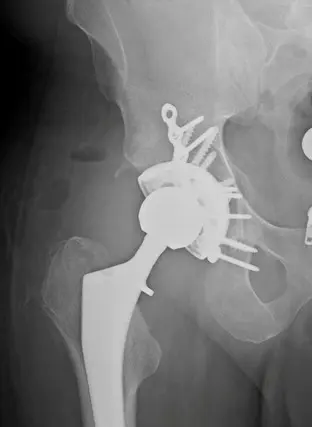

Total Hip Replacement – Before and After Images

Combined surgical fixation acetabulum and total hip for geriatric acetabulum fracture

Combined surgical fixation acetabulum and total hip for geriatric acetabulum fracture